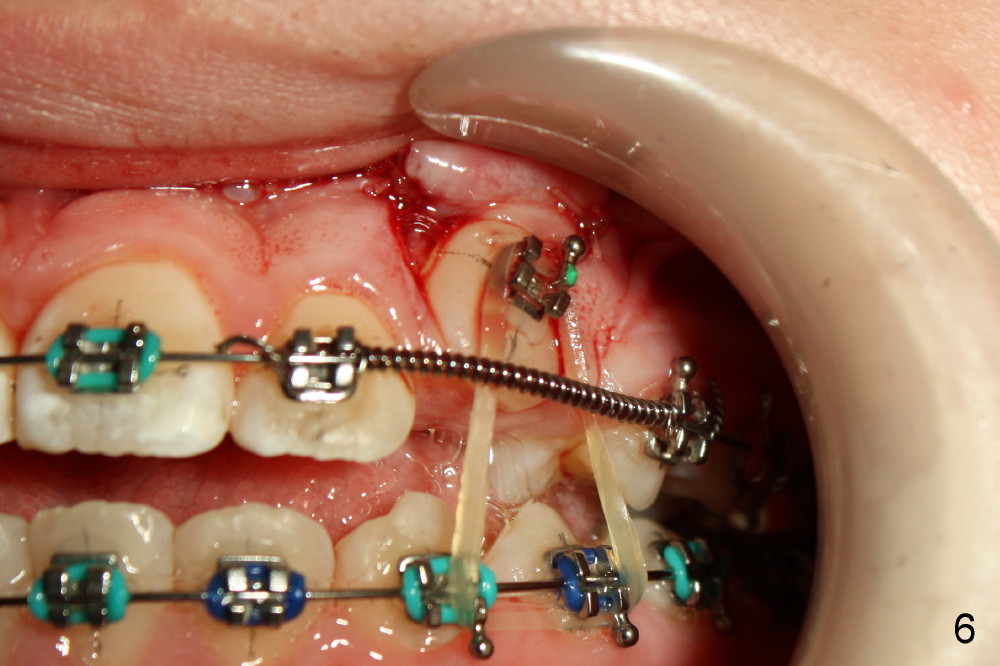

Two oblique incisions were made mesial and distal to UR3 (Fig.3). The mucoperiosteal flap (Fig.3 arrow; Fig.4 F) was raised and pushed apically for bracket placement. Following extraction of UR C, one-fourth inch elastics were placed between U3 and L3,4 (Fig.5,6). The patient was instructed to wear the elastics 24 hours per day. The upper wire is .018 ss with open coil springs, while lower .020.